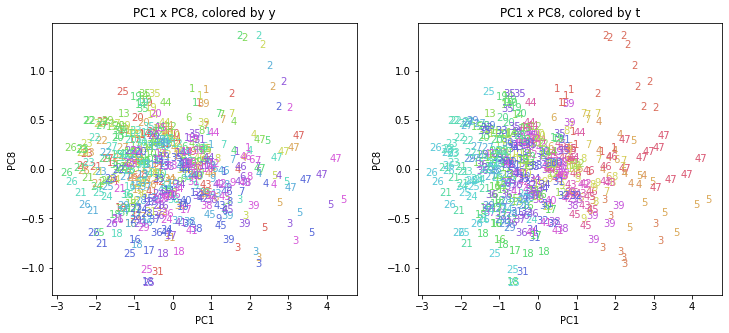

PCAの結果の第n主成分をPCnと表記します。

医療費データの場合と同様に、PCAの結果を見やすく表示するため、seabornのカラーパレットを使って、年月別、都道府県別に色分けして図示してみます(左側が年月別に色分け、右側が都道府県別に色分け)。PC1~PC8まで表示しました。

都道府県番号の表示

上の色分けだけでは都道府県が区別しにくいので、医療費データの場合と同様に、点の代わりに都道府県番号をプロットした図も描いておきます(色分けは上と同じ)。

医療費データの場合ほどはっきりとはしていませんが、PC2が概ね時間の経過を表す成分で、残りの成分が時点によって変わらない地域の特徴を表す成分となっているようです。

また、PC1×PC3を見ると、47沖縄が他の都道府県からかなり離れたところに位置しており、沖縄の地域差が際立っているのが分かります。これは、以前別の記事で年齢階級のない健診データでPCAを実行した場合と似た結果となっています。